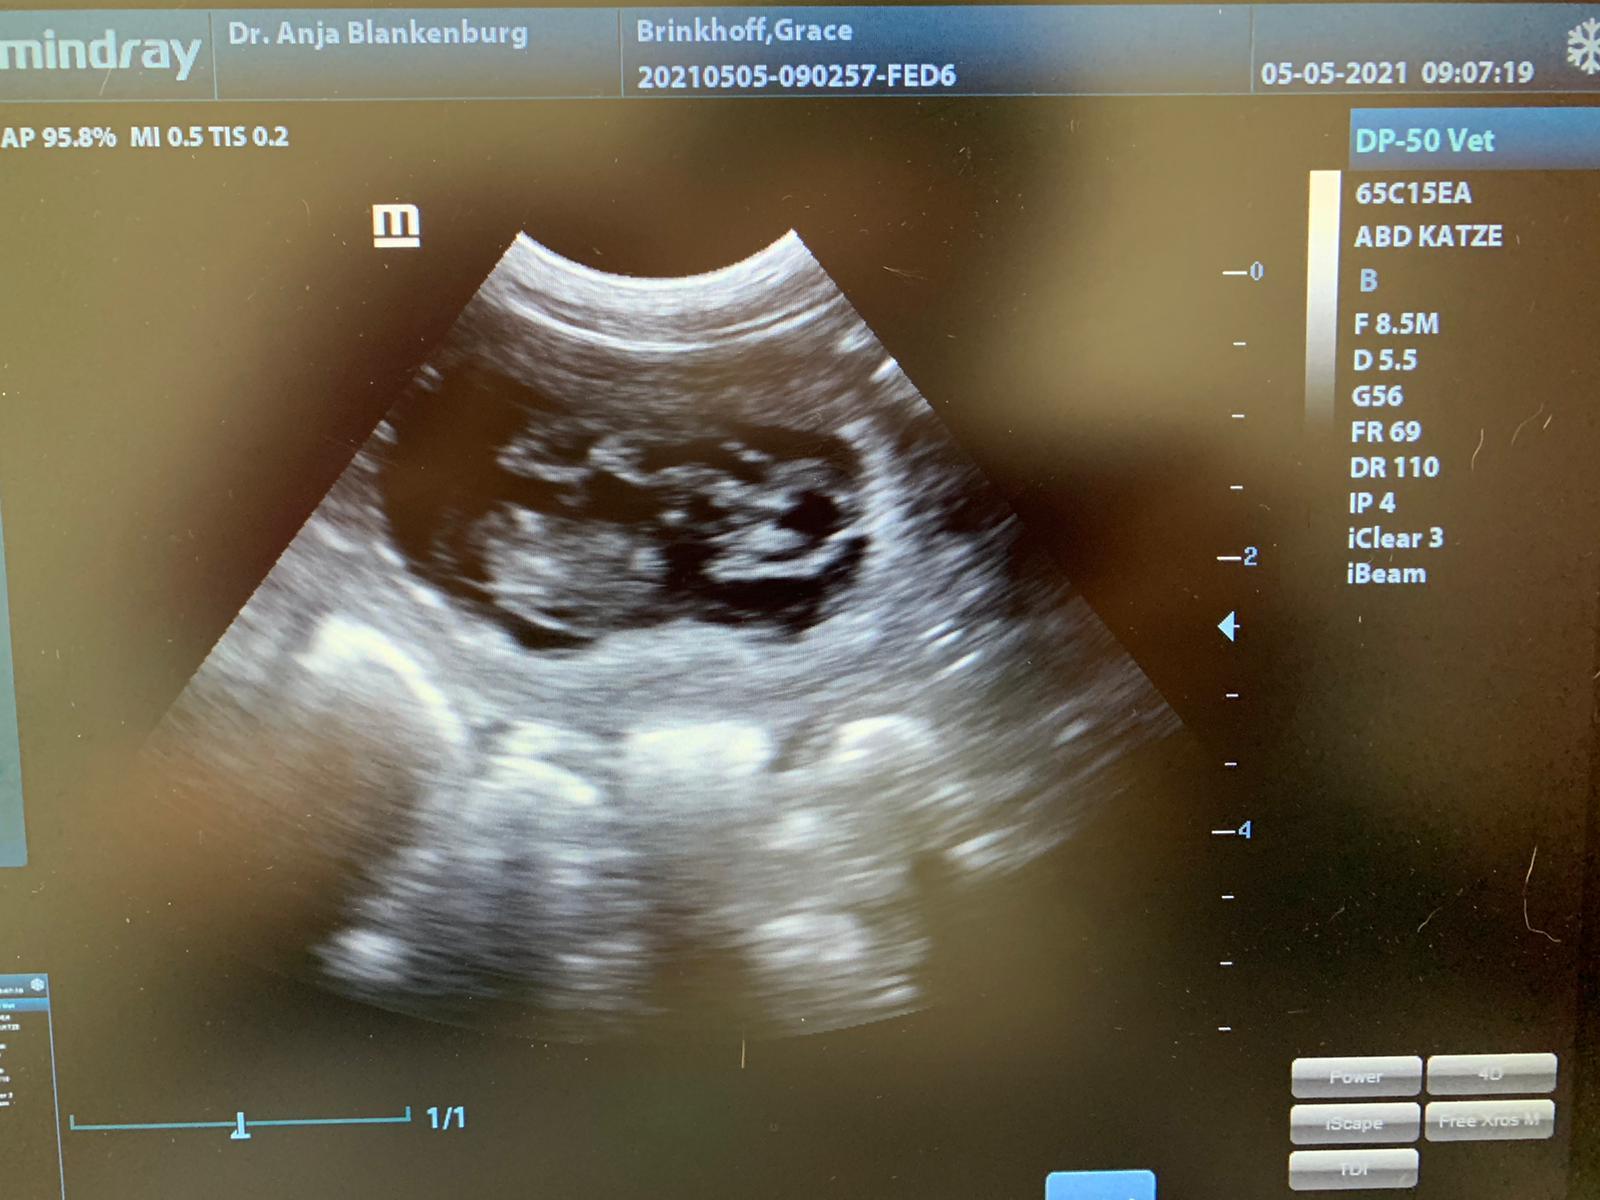

05. Mai 2021, 31. Trächtigkeitstag

Jetzt können wir das Geheminis endlich lüften - Grace ist definitv tragend! Und den Rüden können wir somit auch endlich bekannt geben! Grace of Angel´s Home U are my Destiny- "Rio" war unser Plan B - schon länger hatte ich den hübschen jungen Kerl auf der Liste. Ich wollte Rio etwas später einsetzen - aber er sollte jetzt schon zum Zug kommen! Wir sind sehr happy, dass es alles geklappt hat und freuen uns jetzt, in ca 4 Wochen die F(antastischen)´s begrüßen zu dürfen!